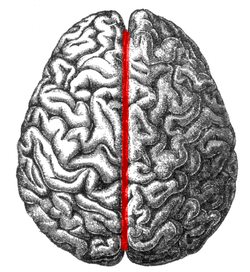

Medial longitudinal fissure

The human brain as viewed from above. Medial longitudinal fissure visible in red, running top to bottom. | |

The medial longitudinal fissure (or cerebral fissure, or longitudinal fissure, or interhemispheric fissure) is the deep groove that separates the two hemispheres of the vertebrate brain.

The medial surfaces of the two hemispheres are as similarly convoluted by gyri and sulci as is the outer surface of the brain.

The falx cerebri, a dural brain covering, lies within the medial longitudinal fissure.

The corpus callosum crosses between the two hemispheres at the bottom of the medial longitudinal fissure.